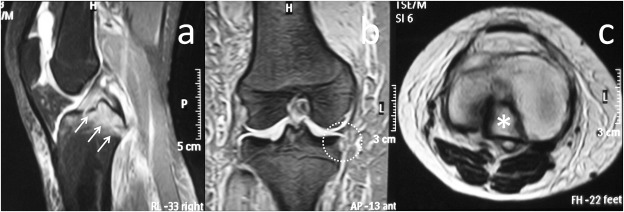

A 20-year-old female was admitted to the emergency department after sustaining a motorcycle accident. On presentation she was unable to weight bear and there was slight knee effusion without ecchymosis or deformity. On physical examination, she was keeping her knee in slight flexion and knee range of motion was painful and grossly restricted. Knee medial joint space was tender and varus stress test at 30° of knee flexion demonstrated grade I medial laxity (medial joint space opening less than 5 mm). Further detailed physical examination could not be performed due to intentional guarding, pain and muscle spasm. Plain radiographic examination of the knee demonstrated a marginal fracture of the anteromedial tibial plateau and lateral intercondylar eminence (Fig. 1 ). MR imaging of the knee revealed PCL avulsion fracture, ACL grade II strain and MCL grade I strain. Both menisci were intact (Fig. 2 ).

Fig. 2

Fig. 2.

MR imaging of the patient at initial admission. (a) Sagittal T2-weighted MR image shows the PCL avulsion from the tibia with marked edema. (b) Coronal T2-weighted MR image medial capsular avulsion fracture (reverse Segond fracture ) and intact medial meniscus (white circle) . (c) T1-weighted MR image demonstrates the fracture fragment clearly (white asterisk ).